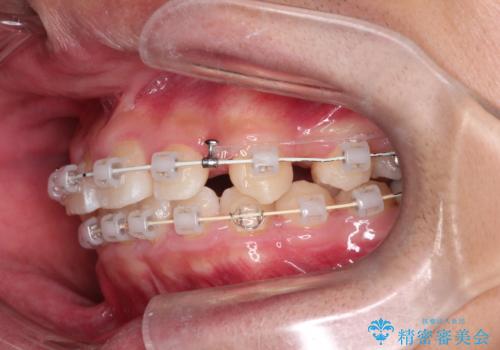

矯正の精密検査の結果上顎左右4番の計2本を抜歯し、審美性に配慮したワイヤー矯正装置(審美装置)を用いて治療を行いました。

八重歯などの歯列のデコボコが綺麗に改善され、患者様にも大変喜んでいただけました。また、咬み合わせが深い「ディープバイト」も併せて改善し、見た目だけでなく機能面でもバランスの取れた咬合を獲得しています。

- ワイヤー(審美装置)

- 2年